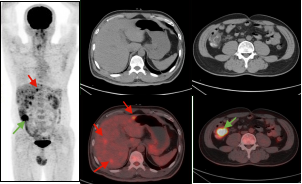

男,56岁,CEA: 40.5ng/ml,图A:肝脏多发转移瘤(红色箭头),图B:显示结肠肝曲高代谢肿块(绿色箭头),经肠镜证实为结肠腺癌。

右肺下叶肺癌伴阻塞性肺炎患者,CT难以精准指导穿刺,而PET/CT可准确区分肿瘤组织及炎性病变。绿色箭头示炎性组织,红色箭头示高代谢区域为肿瘤组织。